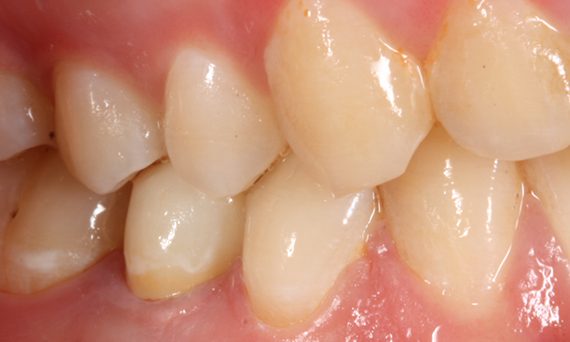

Before: Tooth 26 presenting decay and a failing direct composite restoration.

After: Highly esthetic and functional lithium disilicate ceramic crown.